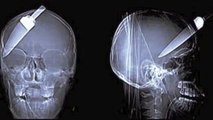

Most bizarre things found on x_rays